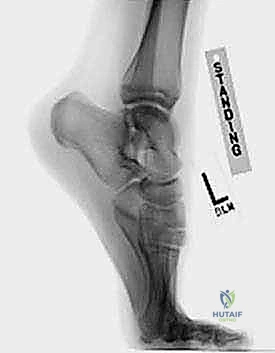

- الأشعة السينية (X-rays): لالتقاط صور دقيقة تظهر وجود العظمة المثلثية (Os Trigonum) أو كسر في بروز ستيدا.

هذه الحالة، وإن كانت شائعة، إلا أنها غالباً ما تُشخص بشكل خاطئ على أنها مجرد التواء بسيط أو إجهاد عضلي، مما يدخل المريض في دوامة من العلاجات غير المجدية والألم المستمر. الكاحل هو مفصل معقد للغاية، وعندما يتعرض لضغط متكرر ومفرط—خاصة عند ثني القدم بقوة نحو الأسفل (وهو ما يُعرف طبياً بالانثناء الأخمصي)—فإن هذا الضغط المستمر يؤدي إلى احتكاك وتلف في الأنسجة الرخوة أو العظام الصغيرة المتواجدة في مؤخرة الكاحل.

في بعض الأحيان، يولد الإنسان بعظمة إضافية صغيرة جداً في مؤخرة الكاحل تُسمى "العظمة المثلثية" (Os Trigonum). في الحالات الطبيعية، لا تسبب هذه العظمة أي مشاكل. ولكن عند الرياضيين أو الأشخاص الذين يمارسون حركات تتطلب ثني القدم للأسفل بقوة، تنحشر هذه العظمة بين عظمة العقب (الكعب) وعظمة الساق، مما يسبب التهاباً شديداً.